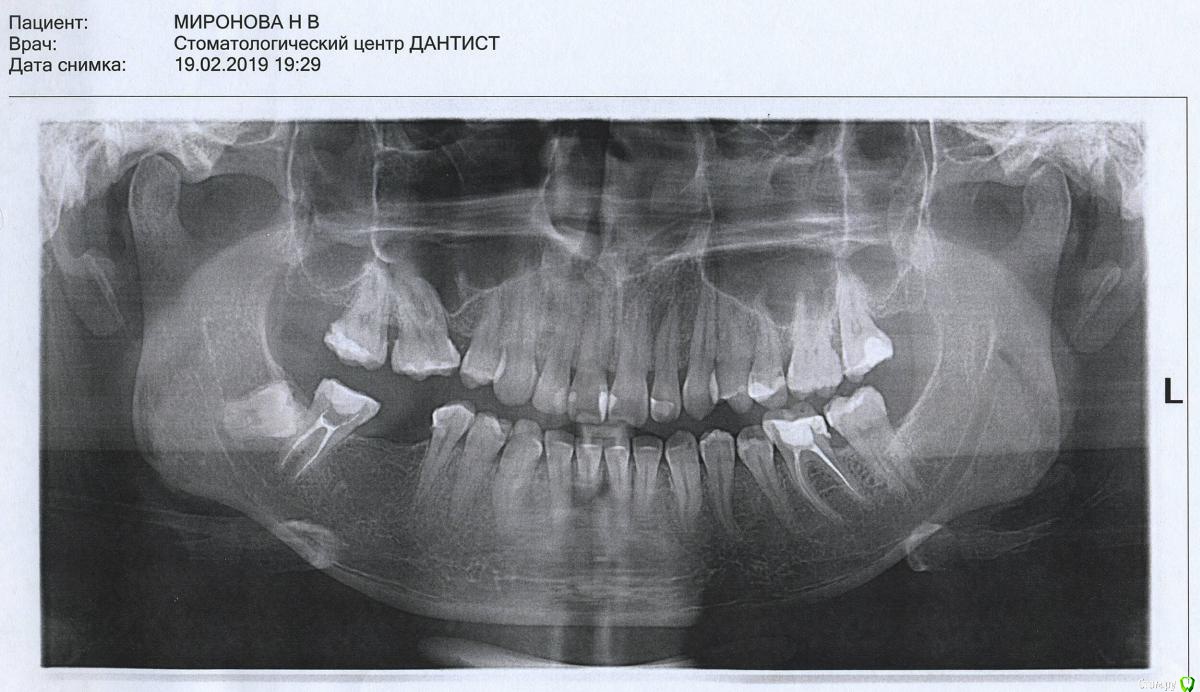

suballex Опубликовано 22 февраля, 2019 Поделиться Опубликовано 22 февраля, 2019 Дорогие врачи, можно попросить Вас, пожалуйста, структурированно ответить мне. А то я запуталась) сейчас сформулирую еще раз по номерам и фото/снимок прицеплю в это сообщение. Имплантацию 46 сейчас не рассматриваю совсем, понимаю что это лучше, но в ближайшие 5, а то и 10 лет - никак. 45 зуб депульпироваться не будет. Коронки цирконий. Аллергия на всю металлическую бижутерию, опухание, покраснение, в анамнезе присутствует пищевой отек Квинке. С золотыми украшениями дружу. Серебро не носила.Предпочтительнее восстановить 47 вкладкой. Не штифтовой. Обычная керамическая по типу оверлей.Установить имплант 46.Я резко не согласен с тем, что "без шестого можно жить". Шестой зуб - основной жевательный. Не нужно забывать, что верхний шестой в стороне не останется. Он будет смещаться в сторону отсутствующего собрата. Это, в результате может привести к необходимости удаления абсолютно интактного зуба.Мост 47-45, это сильно кажущаяся экономия бюджета. Вернее, в краткосрочном периоде вы потратите меньше. Но в долгосрочной перспективе - намного больше. Ну и здоровый пятый запихнете в саркофаг. Ссылка на комментарий

Pavel-Pskov Опубликовано 22 февраля, 2019 Поделиться Опубликовано 22 февраля, 2019 Как я понял большую часть в схеме с имплантом играет нрк, хотя по орте я особых проблем не увидел, ну да во рту виднее. Ссылка на комментарий

nataganka Опубликовано 24 июня, 2019 Автор Поделиться Опубликовано 24 июня, 2019 Или если он меня никак не беспокоит вообще в моем возрасте (35 лет) его можно не трогать? Я даже не подозревала, что он у меня существует, пока на снимке не увидела)))) Интересует компетентное мнение) удалять или нет, и перед имплантацией (за полгода до начала имплантации хочу удалить, если нужно) или после без разницы? Ссылка на комментарий

nataganka Опубликовано 9 декабря, 2019 Автор Поделиться Опубликовано 9 декабря, 2019 Нет, ну я точно перешла дорогу какой-то зубной феечке, у меня уже смех истерический))))) ладно бы гигиену не соблюдала, но нет ведь, и нитью пользуюсь после еды, и ирригатором пользуюсь и щетка электрическая))))))) видимо и впрямь наследственность такая штука коварная. В общем, не успела я заняться удалением ретинированного 48-го зуба... так как теперь финансы потекли в зуб 27. И полугода не прошло. У меня там была пятилетней давности пломба, которая не вызывала ни у кого вопросов собственно на осмотрах и лечении зубов все начало этого года. В ноябре откололся кусочек пломбы, при том ела обычную пищу, не твердую. Под ней внутри зуба оказалась кариозная полость и довольно таки обширная, глазом пока пломба не откололась ее не было видно ни одному врачу, коих я посетила за этот год множество (( Так вот теперь предстоит лечение, либо обойдется пломбой, либо снова депульпация и коронка с вкладкой. По снимку врачи сказали, что на грани, все станет ясно на лечении. Как мне снять карму со своих зубов, чтобы денег хватало на жизнь и одежду, а не относила все финансы в стоматологию? Вопрос походу риторический))))))))))А теперь вопрос фактический, если все-таки будут депульпировать, то можно ли потом это все закрыть керамической реставрацией, а не вкладку+коронку? Сфоткать во рту у меня не получится, по причине расположения зуба. Снимок с предыдущей страницы. Зуб и кариозная полость отмечена Ссылка на комментарий